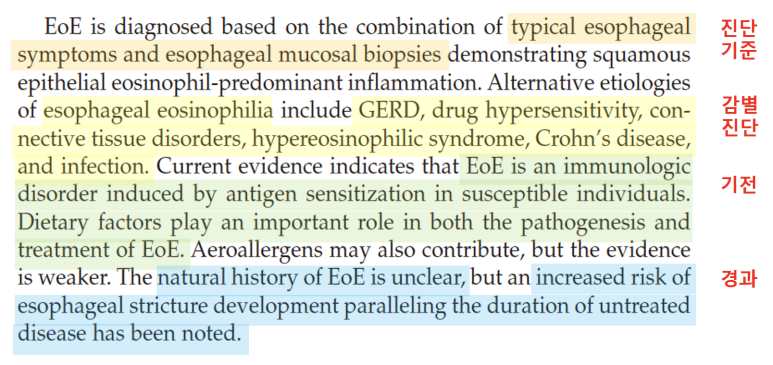

오늘부터 호산성 식도염에 대해서 알아보겠습니다.글을 쓰다 보니, 호산구의 식도염에 대해서 언급해야 할 것이 생각보다 많아 GERD처럼 파트를 나누어 설명하고 싶습니다.Introduction우선 해리슨의 교과서에서 호산성 식도염에 대해서 어떻게 기술하고 있는지 봅시다. 호산성 식도염은 말 그대로 식도에 염증이 생기는 질환입니다. 대표적인 증상은 흉통, 복통, 오심, 복통, 복통, 복통, 이해 곤란, 성인의 경우는 PPI에도 반응이 없는 heartburn(가슴이 타는 듯한 느낌)이 주된 증상입니다. 알레르기 질환(음식 알레르기 천식 두드러기, 알레르기 비염 등)의 대부분이 환자에 따른, 말초 혈액에서 호산성의 수치가 올라가는 경우가 환자의 50%까지 보고되고 있습니다. 내시경 소견은 스코프 스코프(스코프)당 15개 이상의 호산성이 확인되고 진단 가능합니다.

조직검사는 유럽의 경우 6개소를 시행할 것을 권고하고, 미국의 경우 2-4개의 promixal, distalesophagus에서 시행할 것을 권고하고 있습니다.진단 기준 상의 내용을 종합하여 호산구 식도염의 진단 기준을 확인하게 됩니다.먼저 전 세계에서 모여 만든 AGREE 컨퍼런스에서는 식도의 Dysfunction이 발생하는데 아토피 소인이 있고 내시경적으로 특징적인 소견이 있으며 조직학적으로 HPF당 15개의 호산구가 확인되어야 합니다. 이때 중요한 것은 호산구의 침착이 식도에만 국한되어야 하며 다른 2차적인 원인에 의해 식도 내 호산구가 증가하지 않는 것입니다. 즉, 다른 질환 없이 식도로만 호산구가 증가한다는 것을 의미합니다.

즉, 식도 관련 증상이 있을 경우 내시경을 실시하고 조직검사에서 HPF당 15개 이상의 호산구가 있을 경우 식도 내에 호산구를 증가시키는 질환이 모두 제거된다는 가정 하에 호산구 식도염이라는 진단명을 붙일 수 있습니다.

요약 정리하면 호산구 식도염은 전형적인 식도 증상과 식도 조직 검사를 통해 얻은 병변의 특징으로 진단되며 GERD, 감염, 크론병과 같은 식도 내 호산구를 증가시키는 질환을 제거해야 합니다. 호산구 식도염은 감수성이 있는 사람에게 항원에 노출되면 나타나는 면역 반응입니다. 특히 호산구 식도염에서 음식물의 역할은 호산구 식도염의 병태 메커니즘과 호산구 식도염을 치료하는데 중요합니다. 치료에 대해서는 다음 포스팅에서 구체적으로 이야기할 예정입니다.호산구 식도염의 경과는 아직 분명치 않지만 치료하지 않을 경우 질병의 지속과 함께 식도섬유화가 발생하고 섬유화 단계에서는 식도확장시술 외에는 다른 치료방법이 없기 때문에 조기 발견 및 치료하는 것이 중요합니다.